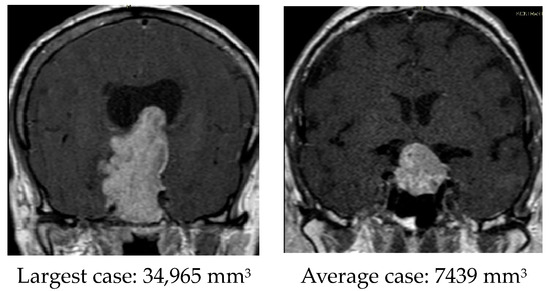

| Tumor size, mm3 | 7802 (2577–11,261) | 5130 (2344–6026) | 10,473 (3753–16,273) | 0.041 |